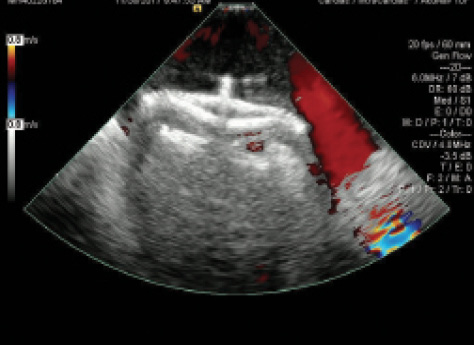

Figure 1. PFO with atrial septal aneurysm. There is wide opening of the septum primum, much larger than is usually seen with most PFOs.

Now, 2 years later, the patient wishes to start a family and is reconsidering her aspirin therapy. No additional events have been reported since the patient has been off contraceptives. TEE was performed again and showed a large PFO with atrial septal aneurysm (Figure 1) and large right-to-left shunt (Figure 2). Treatment proceeded with implantation of a 35-mm Amplatzer PFO occluder (Abbott Vascular) without any complications (Figure 3).